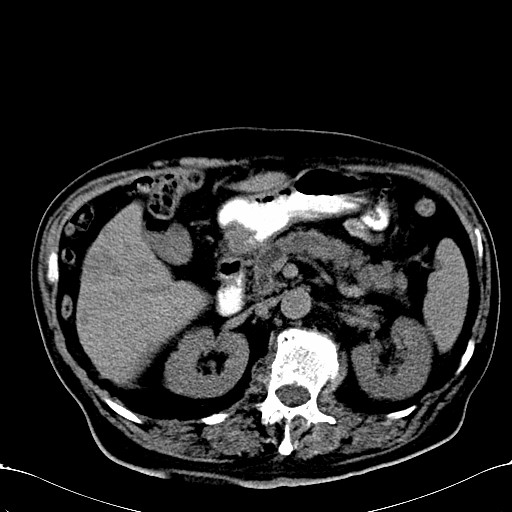

标题: CT28270:胰管扩张,肝多发占位 [打印本页]

标题: CT28270:胰管扩张,肝多发占位

患者,男,75岁。

考虑胰腺钩突癌并肝内转移,建议强化明确。

1)考虑胰头癌并肝脏多发性转移;建议行ct增强扫描检查。2)胃窦癌?建议行胃镜检查。

胰管有扩张,位置比较低,同意楼上几位高手意见。肝内转移可能大,建议增强。

肝脏多方低密度结节,边缘模糊,考虑多发转移,胰管明显扩张,建议增强扫描钩突情况

肝脏多发低密度灶,胰头似呈低密度,胰管扩张,建议增强,

胰管显著扩张,但胆总管未见扩张征象,不太符合胰头占位!考虑慢性胰腺炎.胃窦占位并肝内转移可能!mrcp胃镜增强一起上!